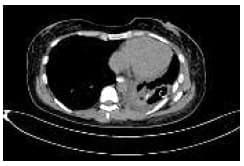

Al segundo día postquirúrgico presenta salida de material alimentario por las sondas de tórax, lo que establece presunción diagnóstica de fístula gastro-pleural, que luego se documenta por endoscopía (Figuras 1 y 2), tomografía computarizada (Figura 3) y estudio contrastado de vías digestivas altas (Figura 4).

Figura 3. Tomografía computarizada donde se aprecia la colección pleural izquierda producto de la fistula. |